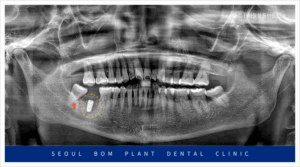

이 환자분의 상태를 정밀하게 검사하기 위해

파노라마 촬영을 진행한 결과,

아래턱 오른쪽 두 번째 어금니(#47) 주변에

심각한 염증이 확인되었습니다.

이 염증이 하치조 신경관까지 영향을 미쳐,

방치할 경우 주변 조직과 다른 치아에까지

영향을 미칠 수 있는 위험한 상황이었습니다.